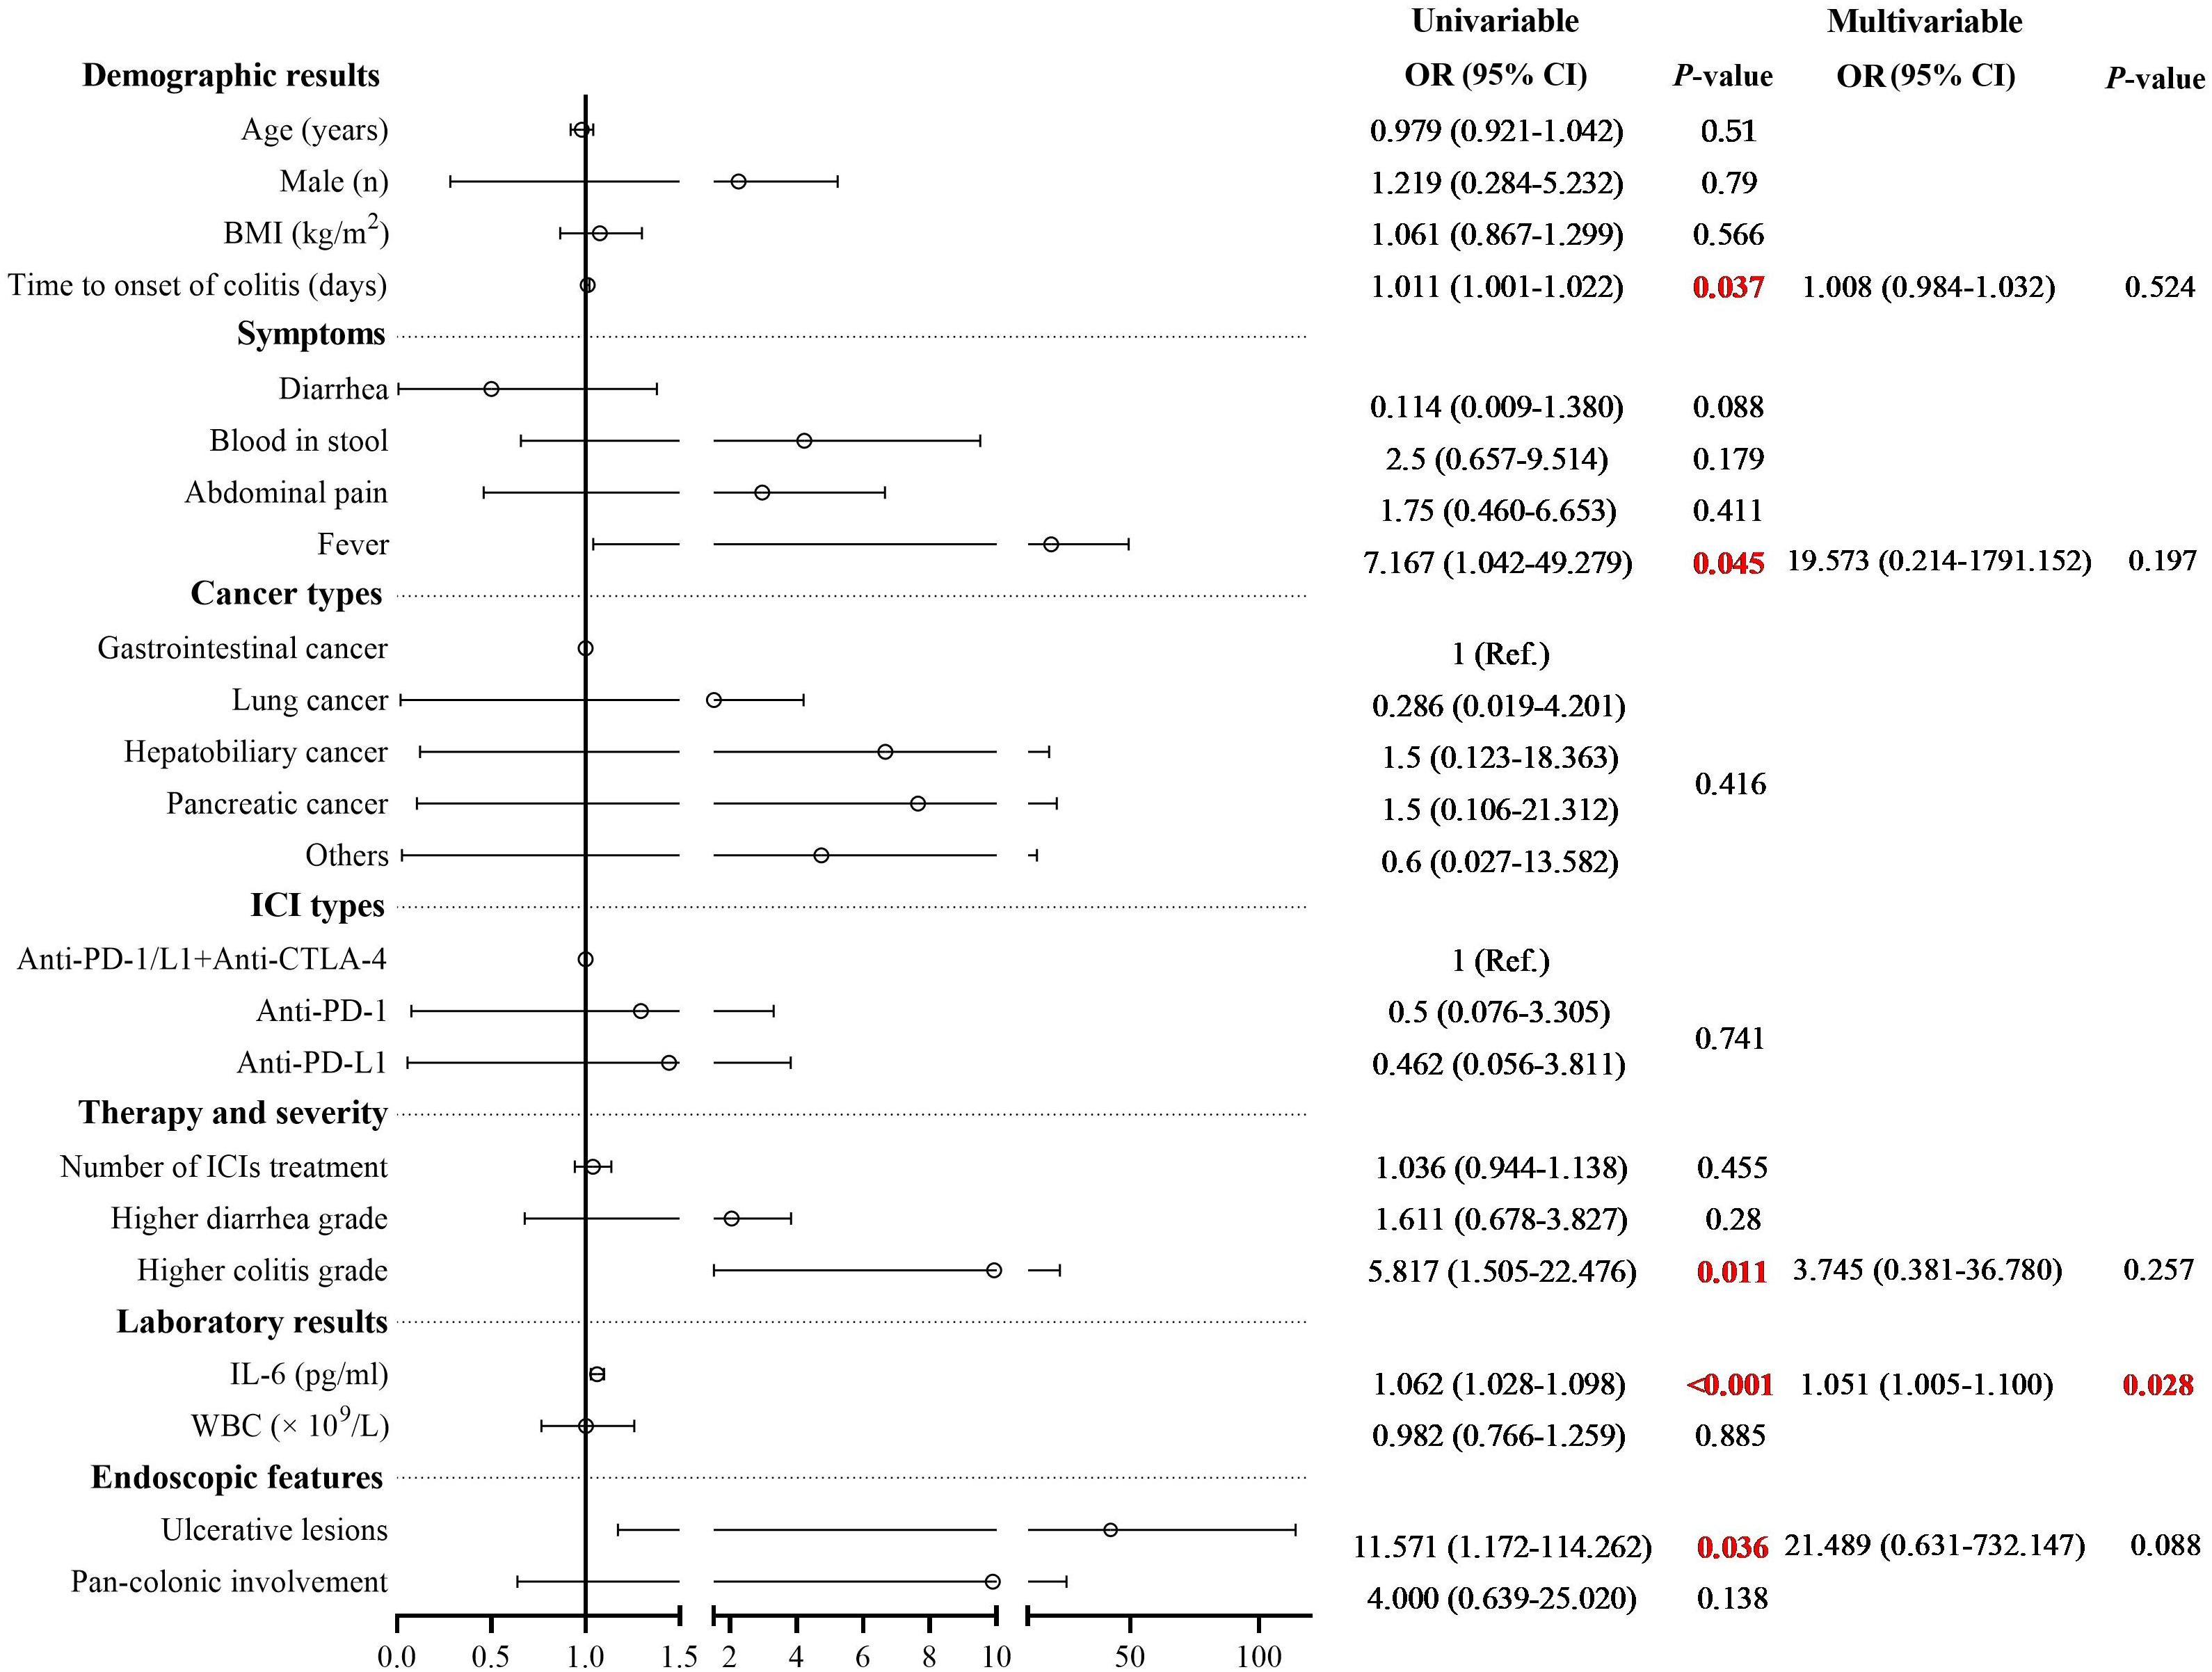

Results: A total of 57 patients were included, with 45 patients in the steroid-responsive group and 12 patients in the steroid-refractory group. Univariate analysis revealed differences between the two groups in the time to colitis onset (median days: 97 vs. 141, P = 0.037), presence of fever (4.4% vs. 25.0%, P = 0.045), presence of ulcerative lesions (26.9% vs. 34.6%, P = 0.036), grades of colitis (P = 0.011), and serum interleukin-6 (IL-6) level (24.1 ± 20.5 pg/mL vs. 81.7 ± 38.7 pg/mL, P < 0.001). Multivariate regression analysis indicated that serum IL-6 level was an independent risk factor for steroid-refractory. Kaplan-Meier survival analysis showed no significant difference in survival time between the two groups.

Multivariate analysis and survival analysis

Multivariate logistic regression analysis was performed to identify risk factors associated with poor response to corticosteroid therapy. Univariate analysis indicated that longer time to onset of colitis (OR: 1.011, 95% CI: 1.001-1.022, P = 0.037), presence of fever (OR: 7.167, 95% CI: 1.042-49.279, P = 0.045), presence of ulcerative lesions (OR: 11.571, 95% CI: 1.172-114.262, P = 0.036), higher colitis grade (OR: 5.817, 95% CI: 1.505-22.476, P = 0.011), and elevated serum IL-6 level (OR: 1.062, 95% CI: 1.028-1.098, P < 0.001) was associated with poor response to corticosteroid therapy (Supplementary Table 1). Multivariate analysis revealed that elevated serum IL-6 level was an independent risk factor for poor response to corticosteroid therapy in patients with ICI-induced colitis (OR: 1.051, 95% CI: 1.005-1.100, P = 0.028) (Figure 3). During the study period, a total of 30 patients died, corresponding to an overall mortality rate of 52.6%. Among these deaths, 24 patients were attributed to tumor progression, 4 patients were due to cardiovascular disease, and 2 patients were due to pulmonary infection. Kaplan-Meier survival analysis revealed no significant difference in overall survival time between the steroid-responsive group (median 24.0 months, 95% CI: 19.3-28.7) and the steroid-refractory group (median 28.0 months, 95% CI: 21.7-34.3) (P = 0.754) (Figure 4).

Figure 3. Univariate and multivariate logistic regression analysis of risk factors associated with steroid-refractory colitis. Multivariate analysis revealed that elevated serum IL-6 level was an independent risk factor for poor response to corticosteroid therapy in patients with ICI-induced colitis (OR: 1.051, 95% CI: 1.005-1.100, P = 0.028).

This study investigated potential risk factors associated with poor response to corticosteroid therapy in patients with ICI-induced colitis. Univariate analysis revealed that longer time to onset of colitis, presence of fever, ulcerative lesions detected by colonoscopy, higher colitis grade, and elevated serum IL-6 level was associated with poor response to corticosteroid therapy. Multivariate logistic regression analysis demonstrated that elevated serum IL-6 level was independently associated with poor response to corticosteroid therapy in patients with ICI-induced colitis.